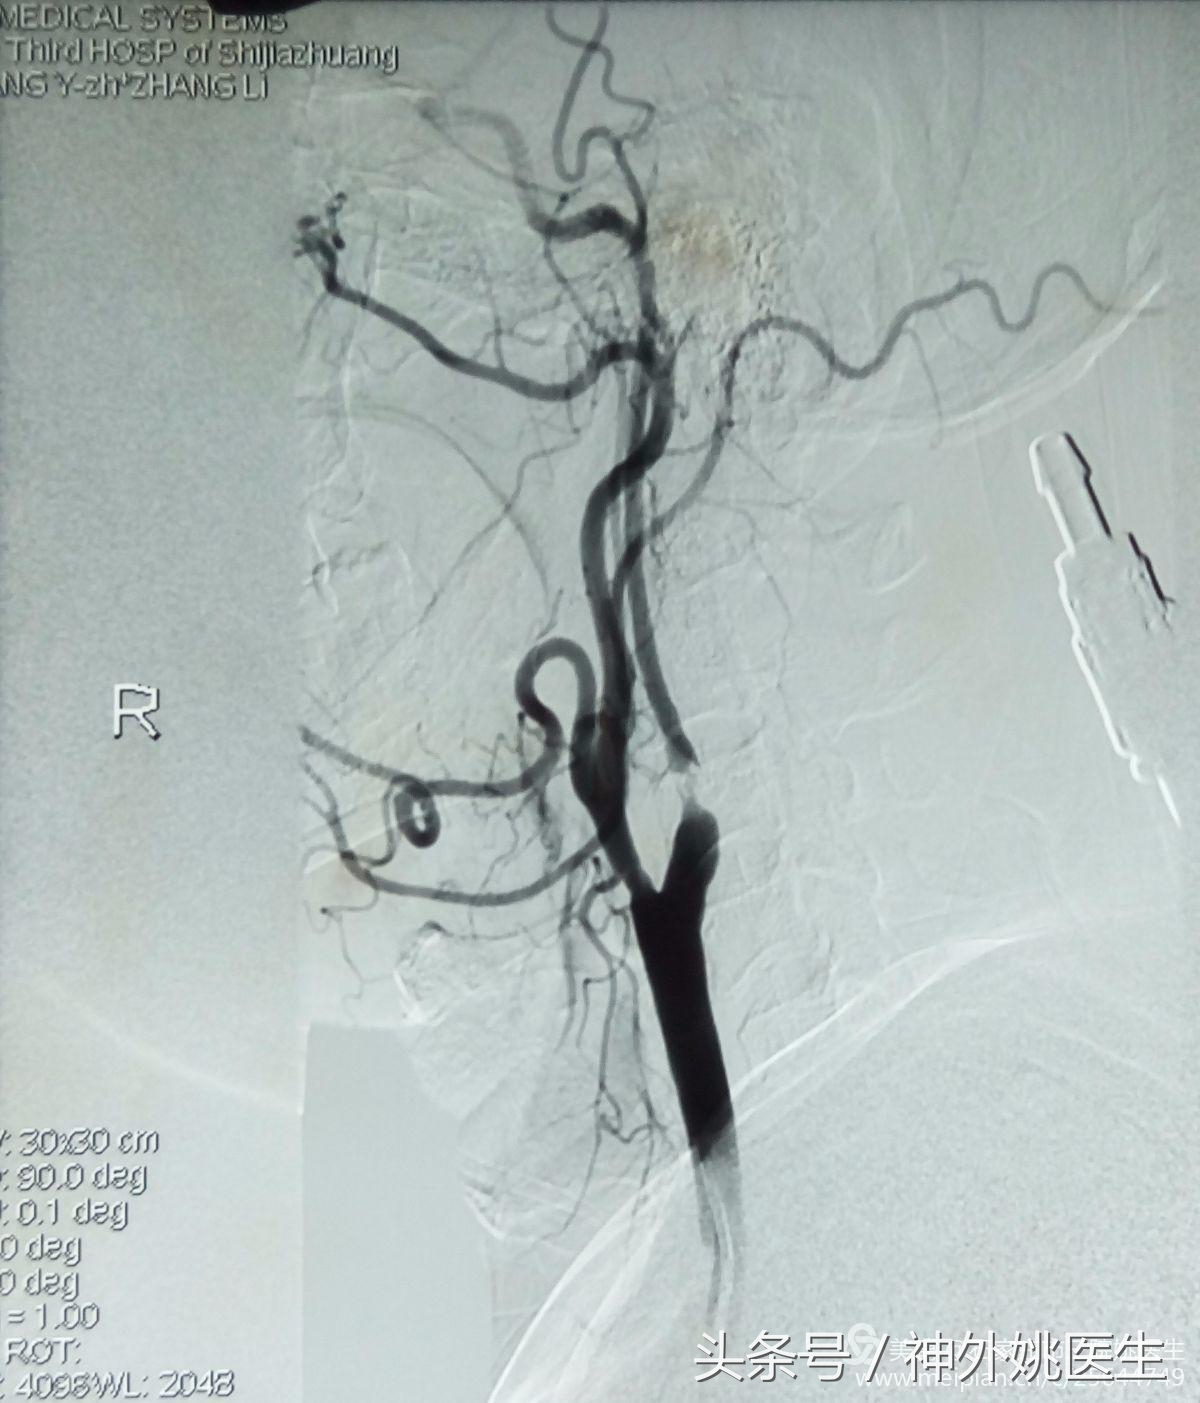

术前评估(DSA):

1.右颈动脉造影示:右颈内动脉狭窄部位位于球部以远,狭窄远端管腔明显变细(图6、图7)。狭窄段远端平下颌角及C2/3椎间盘水平(图8)。提示位置较高,操作难度较大。缝合时需精细操作,避免管径丢失,术后管腔狭窄。

图6

图7

(图8)